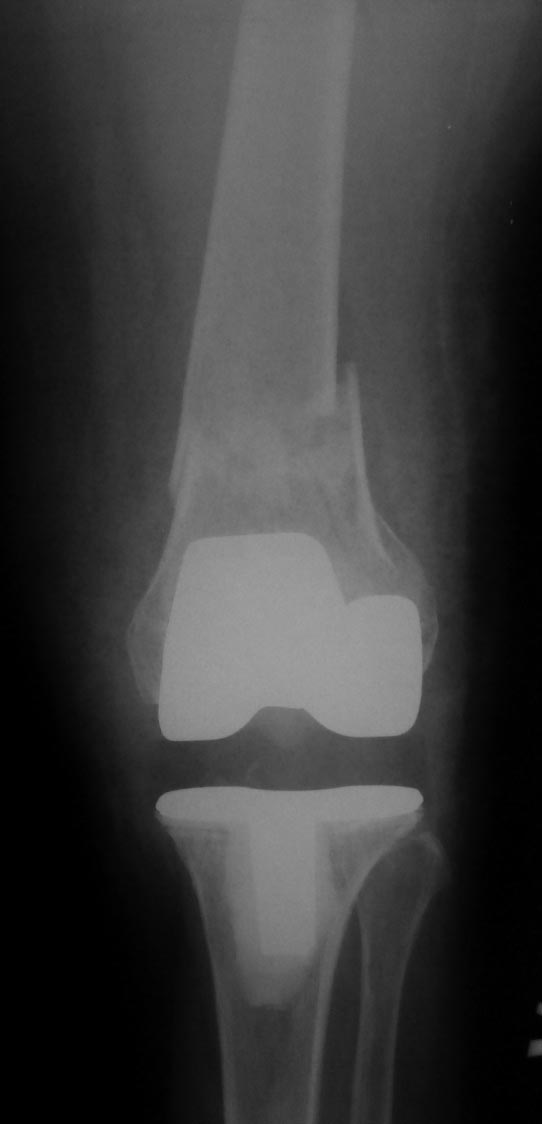

袙芯褌 芯斜械褖邪薪薪褘泄 胁 褔械屑-褌芯 锌芯褏芯卸懈泄 褋谢褍褔邪泄. 袩邪褑懈械薪褌泻邪 58 谢械褌 褋 褌褟卸械谢褘屑

褉械胁屑邪褌芯懈写薪褘屑 邪褉褌褉懈褌芯屑. 袨锌械褉懈褉芯胁邪谢 胁 2013 谐. 袙 芯写薪褍 褋械褋褋懈褞 褋写械谢邪谢

褔褉械褋泻芯卸薪芯 锌芯胁褌芯褉薪褍褞 芯锌械褉邪褑懈褞 薪邪 褋褌芯锌械 (褉邪薪褜褕械 谐写械-褌芯 芯锌械褉懈褉芯胁邪谢懈,

锌邪褑懈械薪褌泻邪 锌褉懈械褏邪谢邪 懈蟹写邪谢械泻邪) 懈 屑邪谢芯懈薪胁邪蟹懈胁薪褘泄 邪褉褌褉芯写械蟹 谐芯谢械薪芯褋褌芯锌薪芯谐芯

褋褍褋褌邪胁邪 (懈屑械谢邪褋褜 胁邪褉褍褋薪邪褟 写械褎芯褉屑邪褑懈褟, 泻邪泻 泻芯屑锌械薪褋邪褑懈褟 胁邪谢褜谐褍褋邪 泻芯谢械薪邪,

薪邪 褎芯薪械 胁褘褉邪卸械薪薪芯泄 褉械胁屑邪褌芯懈写薪芯泄 邪褉褌褉芯锌邪褌懈懈). 袗 褔械褉械蟹 薪械写械谢褞鈥

锌褉芯褌械蟹懈褉芯胁邪薪懈械 泻芯谢械薪薪芯谐芯 褋褍褋褌邪胁邪 (褎懈斜褉芯蟹薪褘泄 邪薪泻懈谢芯蟹 锌芯褋谢械 泻芯谐写邪-褌芯

胁褘锌芯谢薪械薪薪芯泄 褋懈薪芯胁褝泻褌芯屑懈懈, 谐褉褍斜邪褟 胁邪谢褜谐褍褋薪邪褟 写械褎芯褉屑邪褑懈褟). 袩芯薪褟褌薪芯, 褔褌芯

薪械写械谢褞 屑械卸写褍 芯锌械褉邪褑懈褟屑懈 褋褌芯锌邪 褌芯褉褔邪谢邪 胁 褋褌芯褉芯薪褍 懈 薪械 斜褘谢邪

芯锌芯褉芯褋锌芯褋芯斜薪芯泄. 袨褋薪芯胁薪芯械 锌芯卸械谢邪薪懈械 锌芯 泻芯谢械薪泻械 斜褘谢芯, 褔褌芯斜褘 褋谐懈斜邪谢邪褋褜 褏芯褌褜

薪械屑薪芯谐芯 写谢褟 锌芯褏芯写芯胁 胁 褌械邪褌褉. 袙 泻芯薪械褔薪芯屑 褋褔械褌械, 褋褍褋褌邪胁 褋谐懈斜邪谢褋褟 写芯 90 谐褉.

肖芯褌芯谐褉邪褎懈褟 褋褌芯褟 斜褘谢邪 锌褉懈褋谢邪薪邪 褔械褉械蟹 2 谐芯写邪 锌芯褋谢械 芯锌械褉邪褑懈泄. 袗 褔械褉械蟹  3

谐芯写邪, 锌褉芯褕械写褕懈屑 谢械褌芯屑, 锌邪褑懈械薪褌泻邪 褍锌邪谢邪 褋 谢械褋褌薪懈褑褘: 锌械褉懈锌褉芯褌械蟹薪褘泄 锌械褉械谢芯屑

斜械写褉邪. 效械褉械蟹 5 写薪械泄 锌褉懈械褏邪谢邪 芯锌械褉懈褉芯胁邪褌褜褋褟. 袨褌褋褞写邪 芯褌械泻 薪邪 褎芯褌芯 褋褌芯锌褘.